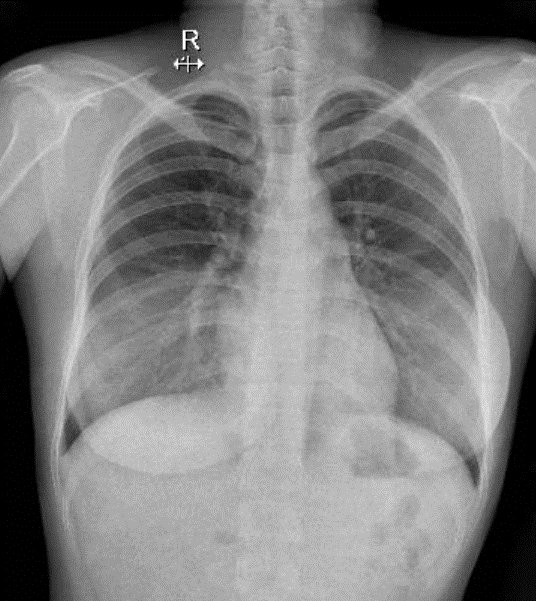

Hãy phân tích tình huống NỮ 27 tuổi -CĐ: Thẩm mỹ

1-Ảnh giả thành ngực hai bên